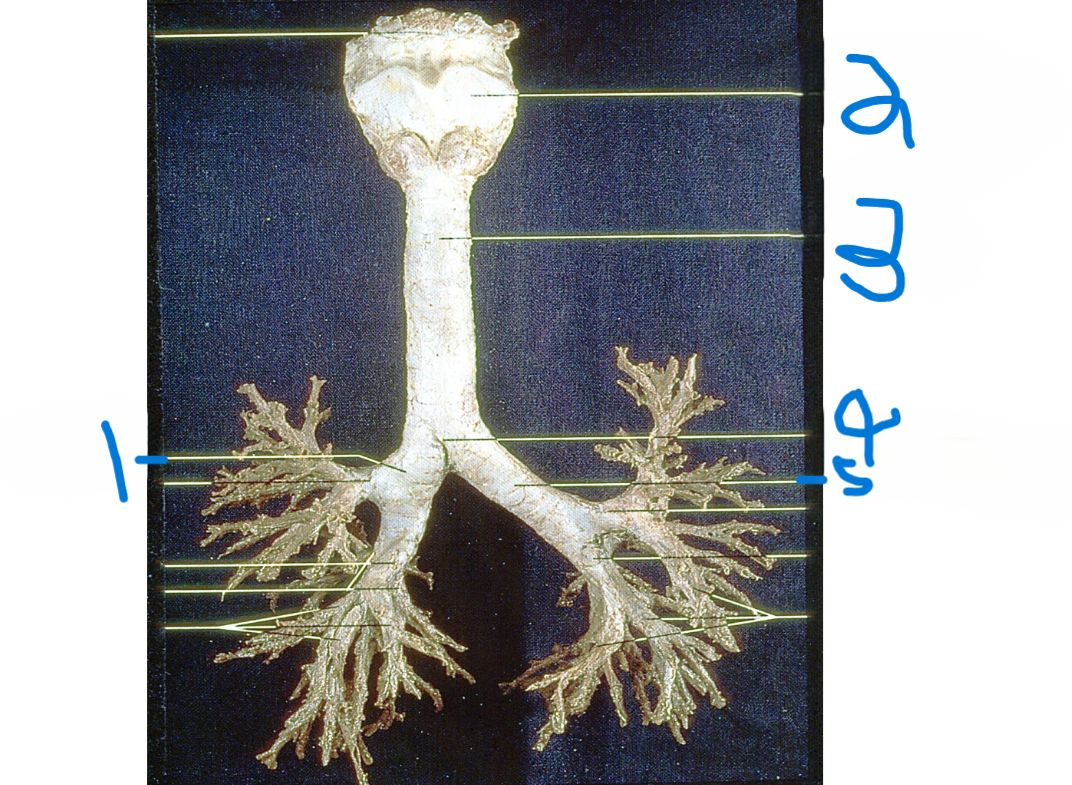

Right main bronchus

What is depicted by #1

Thyroid cartilage

What is depicted by #2

Trachea

What is depicted by #3

Carina

What is depicted by #4

Left main bronchus

What is depicted by #5